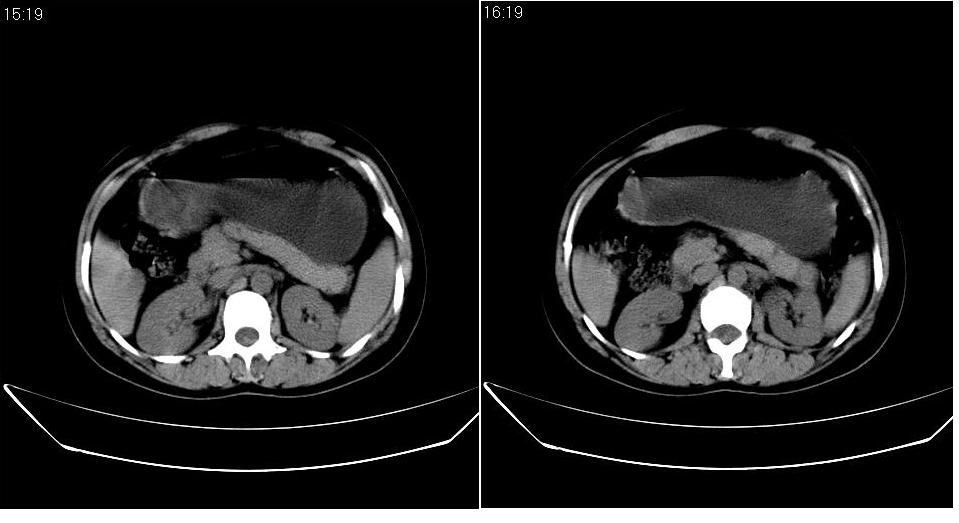

女 36岁,腹痛月余,b超提示肝左叶占位,腹水。

肝脏左叶明显增大,各叶比例失调,左叶实质内不均匀低密度影,似乎有肝内胆管的扩张,没有增强实在不好判断,不知患者肝功能是否正常,我觉得象胆管细胞癌。

从这个平扫图像看,只能诊断肝左叶占位,具体性质没有增强扫描不能诊断,只能说肝左叶低密度影,建议增强扫描进一步检查。

1)考虑肝左叶肝癌;建议行进一步检查。2)肝硬化,脾稍大。3)双侧少量胸腔积液。

肝左叶占位,建议增强。胸腔积液。

肝脏左叶明显增大,且左叶实质内不均匀低密度影。考虑左叶占位??建议增强后再讨论。